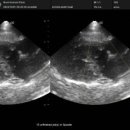

전문 동물 진료, 친절한 서비스 위치 : 강원 양양군 남문로 19 전화번호 : 033-673-4004 진료시간을 꼭 확인하세요 진료시간 바로가기 라온동물병원 양양군 동물병원 라온동물병원 은 양양읍 성안길에 위치하고 있으며, 최신 장비와 다양한 진료 서비스를 제공합니다. 추천 포인트 : X-ray 및 초음파기기 보유, 다양한...